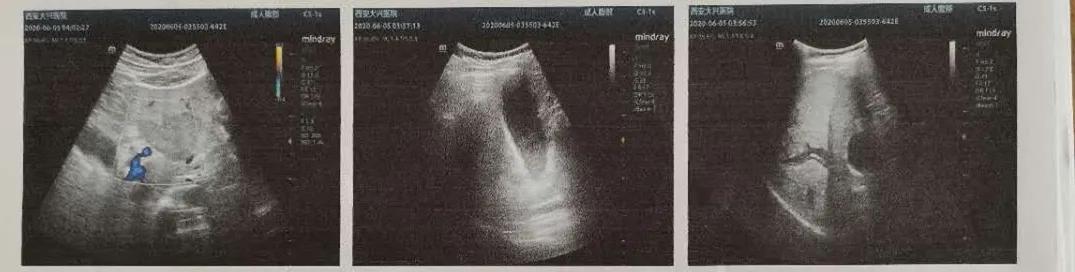

林涛主任决定行超声胃镜检查,但超声内镜对于胆胰病灶的检查操作难度比较大,胆管的直径很细,超声内镜检查的难度更大。经过林涛主任及内镜中心团队的密切配合,在胆总管末端即壶腹部发现了高回声的占位病灶,其后可以看到明显的声影。确认为胆总管末端结石。